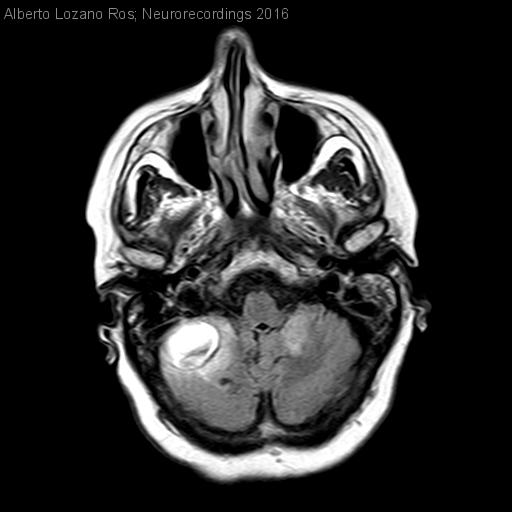

Hematoma cerebeloso. Trombopenia severa autoinmune en paciente con cavernomatosis múltiple hereditaria

Diagnóstico final: Hematoma intraparenquimatoso cerebeloso derecho secundario a trombopenia autoinmune. Cavernomatosis múltiple hereditaria.

Neurología: Patología cerebrovascular

Etiología: Malformación vascular